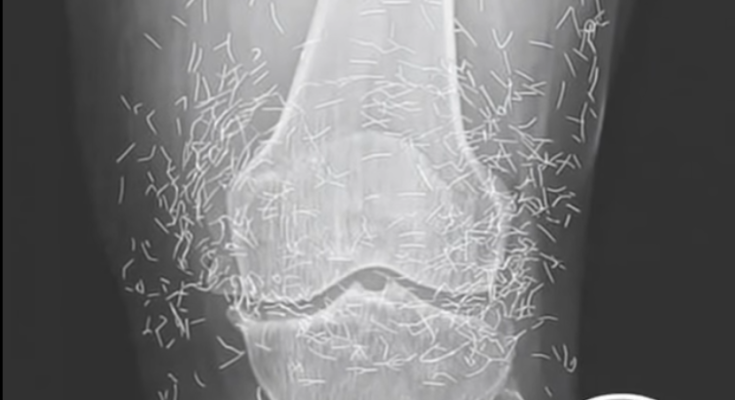

What started as a routine hospital visit for knee pain turned into a medical mystery that left doctors speechless. A 65-year-old woman in South Korea went in expecting a diagnosis of arthritis — but when her X-ray appeared on the screen, the room fell silent. Her knee joint wasn’t just worn down from age; it was filled with dozens of tiny gold needles. The strange discovery sparked immediate questions about how they got there and why they had remained unnoticed for so long.

Doctors soon learned that the woman had been struggling with osteoarthritis for years, a condition that makes everyday movement painful as cartilage breaks down. Frustrated by the limits of conventional medicine, she had turned to acupuncture — a centuries-old therapy believed to ease pain and improve circulation. But instead of using temporary needles, her acupuncturist had inserted fine gold ones beneath the skin permanently, convinced they would provide lasting healing energy.

The shocking X-ray served as a cautionary reminder of how alternative treatments can sometimes go too far. Specialists warn that leaving any metal object inside the body can cause inflammation, infection, and complications during imaging procedures. While acupuncture, when performed properly, is generally considered safe, experts emphasize that permanent implants are not medically approved or supported by evidence.